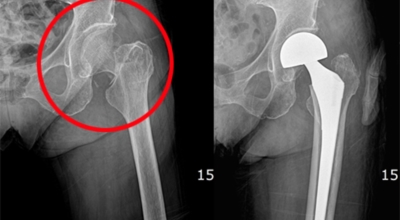

고관절염은 고관절에 나타나는 관절염을 말하며 고관절의 연골이 닳게 되면서 뼈와 뼈가 서로 부딪히며 통증을 일으키게 됩니다. 고관절염 초기 증상으로는 사타구니 부위가 불편하게 느껴지며, 무리하면 통증이 생길 수 있다고 하며, 관절염 증상이 심해지면서 사타구니에서 느끼던 통증이 허벅지와 엉덩이 통증으로 이어지기도 하는데, 고관절염 통증 증상으로 초기에는 허리 통증이 나타나 허리 질환과 혼동하기 쉬우며 각별히 척추질환이 있는 사람은 고관절 통증 증상과 마찬가지로 엉덩이, 다리 통증이 동반되기 때문에 훨씬 헷갈리는 경우가 많다고 해요.

이 증상은 퇴행성 고관절염에 의해 발생하는 현상으로 보통은 중장년층에게 수시로 일어나는 질병입니다. 이 질병은 관절과 관절 사이에 존재하는 연골이 닳아 없어지면 관절 내부와 주위에 염증과 통증을 동반해요. 보통 골반 하단에 뻐근한 증상을 일으키고 양반다리 자세를 할 때 통증이 심해집니다.

더불어 계단을 오를 때 통증이 심해지고 오래 걷는것도 힘들어 집니다. 원인은 노화로 인한 연골 마모, 과체중, 고관절 질환을 방치하는 경우 입니다. 치료방법은 적절한 운동과 소염제를 활용하기도 하며 심할경우 수술 치료가 시행 될 수 있습니다.

3. 고관절 통증 증상 원인 - 퇴행성 관절염

나이가 들면 통상적으로 발생되는 질환 중 한 종류입니다. 관절을 지켜주며 있는 연골의 훼손이나 퇴행성 변화로 인해 관절을 이루는 뼈와 인대 등에 훼손이 생겨 염증과 통증이 나타나는 질환입니다. 고관절 쪽 연골이 닳게 되면서 망가지게 되고 또 쉽게 끊이지 않는 통증에 시달릴 수 있습니다.

고관절 통증 증상 치료법

고관절 통증 치료에는 크게 약물 치료와 물리 치료가 있답니다. 고관절염의 진행을 늦추거나 증상을 개선하기 위한 목적으로 항염증제 또는 진통제를 투여해요. 고관절 질환의 일부 증상은 체외 쇼크파, 물리치료, 약물치료 과 같은 비수술 요법으로 증상이 호전될 수 있습니다.

그러나 비수술 치료법으로 개선시키는 것이 어려운 경우 수술적 방법이 고려되어요. 고관절 통증을 조기에 치료하면 약물치료 외에 물리치료로 약 50% 정도 큰 효과를 볼 수 있답니다. 게다가, 보통 고관절 증상 관리에 보탬이 되는 요가, 수영, 스트레칭은 고관절 예방과 치료에 보탬이 돼요.